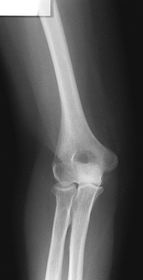

AP Elbow Fully Extended 60-75 kV 40 SID 14x17 IR nongrid CR @ mid-elbow joint MUST SEE entire elbow joint very slight superimposition of radial head by the ulna

Epicondyles must be _____ to the IR for an AP fully extended elbow projection. Parallel